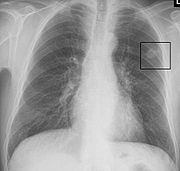

سرطان الرئة

مقالة مفصلة: سرطان الرئة

| سرطان الرئة | ||

| معدل الانتشار | 3.3 مليون (2015)[7] | |

| معدل البقاء 5 سنوات | 17.4% (الولايات المتحدة)[8] | |

| حالات الوفاة | 1.7 مليون (2015)[6] | |

| عوامل الخطورة | تدخين السجائر (يرتبط بنسبة 85- 90% من جميع الحالات)؛ التعرض في مكان العمل لمواد معينة (منها الأسبست asbestos وبعض المواد الكيميائية العضوية)؛ التعرض للإشعاع؛ التعرض لغاز الرادون (لا سيما عند المدخنين)؛ وجود دخان التبغ في البيئة. | |

| العلامات المنذرة | سعال مستمر؛ قشع مختلط بدم؛ تنفس وزيزي؛ ألم كتفي أو صدري؛ انتفاخ (تورم) الوجه أو الرقبة؛ التهاب الرئة أو التهاب القصبات المتكرر. | |

| الكشف والتشخيص | صورة صدر شعاعية، تحليل الخلايا التي في القشع، فحص المسالك القصبية بالمنظار الليفي الضوئي. | |

| العلاج | إن سرطانات الرئة نوعان أساسيان: صغير الخلايا small cell وغير صغير الخلايا. ويعالج سرطان الرئة صغير الخلايا الذي ينتشر بسرعة، بالعلاج الكيميائي وحده أو بالمشاركة مع المعالجة الشعاعية بدلا من الجراحة. يوجَّه الإشعاع نحو الصدر، وفي بعض الحالات نحو الدماغ لقتل النقائل الورمية. وبالنسبة لسرطانات الخلايا (الرئوية) غير الصغيرة الموضّعة، فباستطاعة الجراحين إزالة الجزء المصاب من الرئة على الرغم من أن الانتكاسات شائعة؛ أما بالنسبة للحالات المتقدمة فيمكن استخدام المعالجة الشعاعية أو المعالجة الكيميائية أو المعالجة بالليزر أو بالجمع بين بعض هذه المعالجات عوضا عن المعالجة الجراحية.

| |

| ملاحظات | * انخفض معدل حدوث هذا المرض عند الرجال منذ الثمانينات ولكنه ما زال يرتفع عند النساء.